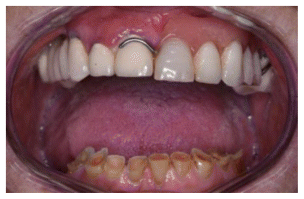

A 76-year-old male patient presented to the authors with an upper skeletal prosthesis and masticatory difficulties.

The patient’s medical history revealed that he was being treated with Ramipril 10 mg tablets for hypertension. The patient underwent both clinical and radiological evaluations.

Intraoral examination and panoramic radiographic assessment (Figures 1 and 2) indicated the need for implant-prosthetic rehabilitation treatment.